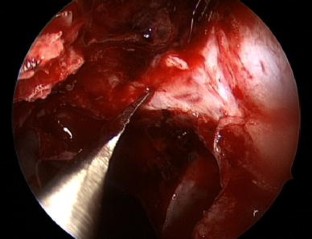

Fig. 2